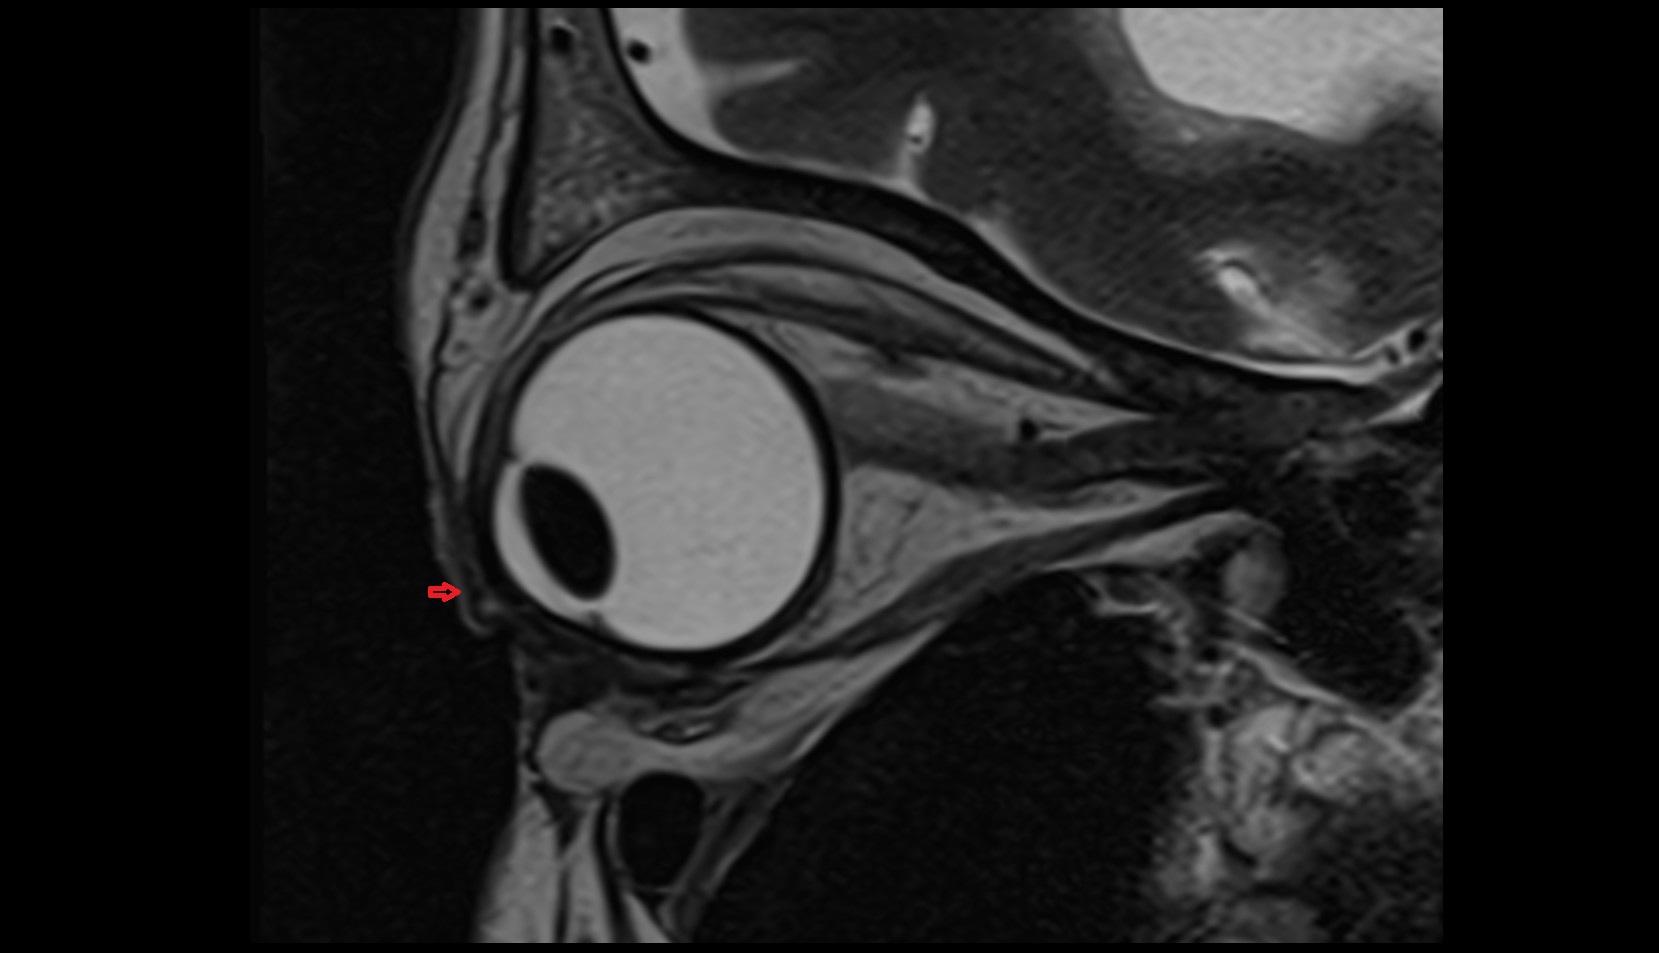

- Uterus

- Body of uterus

- Fundus of uterus

- Cervix of uterus

- Isthmus of uterus

- Endometrium of uterus

- Myometrium of uterus

- Perimetrium of uterus

- Junctional zone of uterus